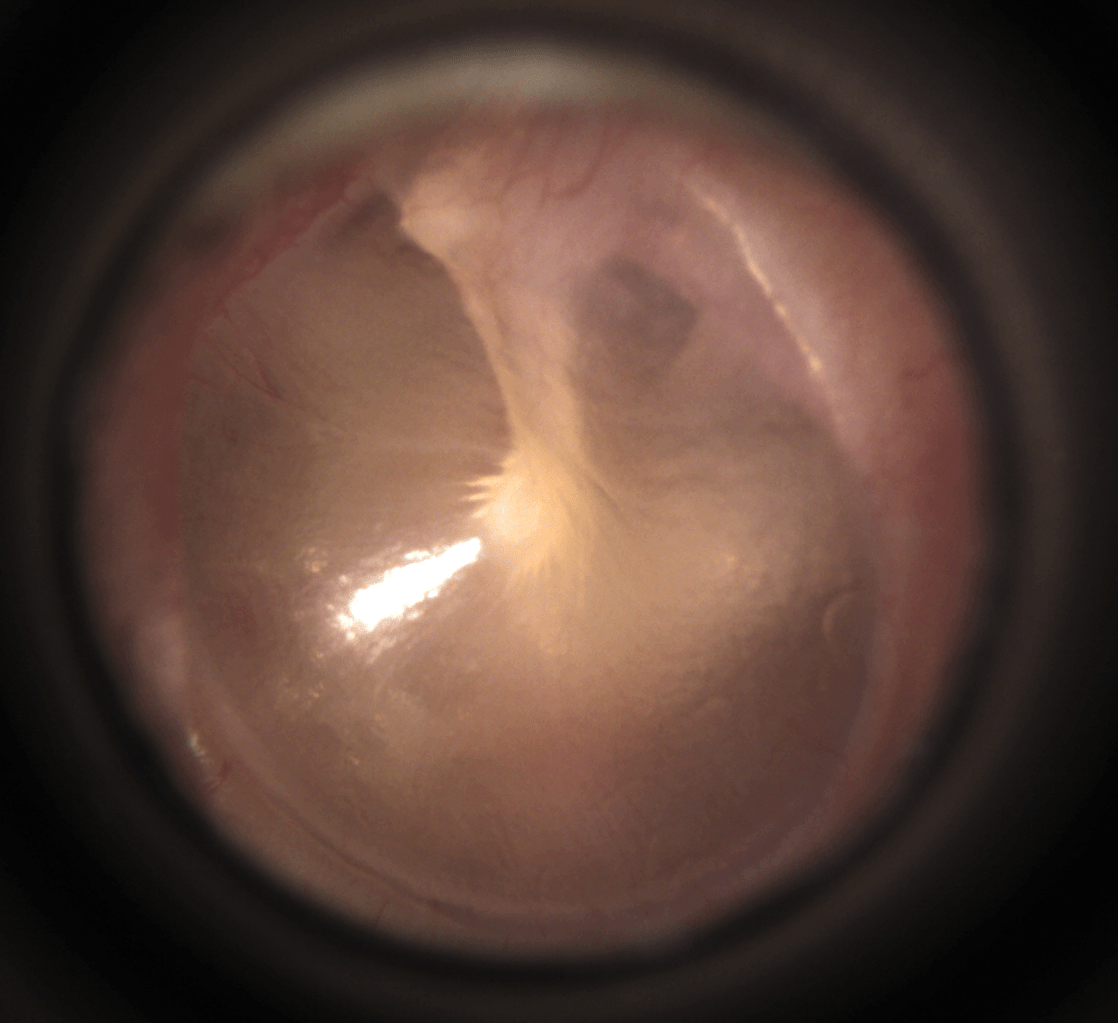

Web the cone of light, or light reflex, is a visible phenomemon which occurs upon examination of the tympanic membrane with an otoscope. Despite what supporters say, there is no. Web the light reflex or the cone of light on the left tympanic membrane is positioned in the 7 o’clock to 8 o’clock direction.

Web ear canal, eardrum, cone of light and malleus bone. The light reflex, or cone of light, is a visible phenomenon. Dichotic listening is the auditory process that involves listening with both ears.dichotic listening….

Web This Cone Of Light Is Located In The Right Ear At 5 O’clock And The Left Ear At 7 O’clock.

The eardrum may be red and bulging if there is an infection. This will be in the 5 o’clock position in the right ear, and in the 7 o’clock. A) inner ear b) middle ear c) external ear d) semicircular ear, the.